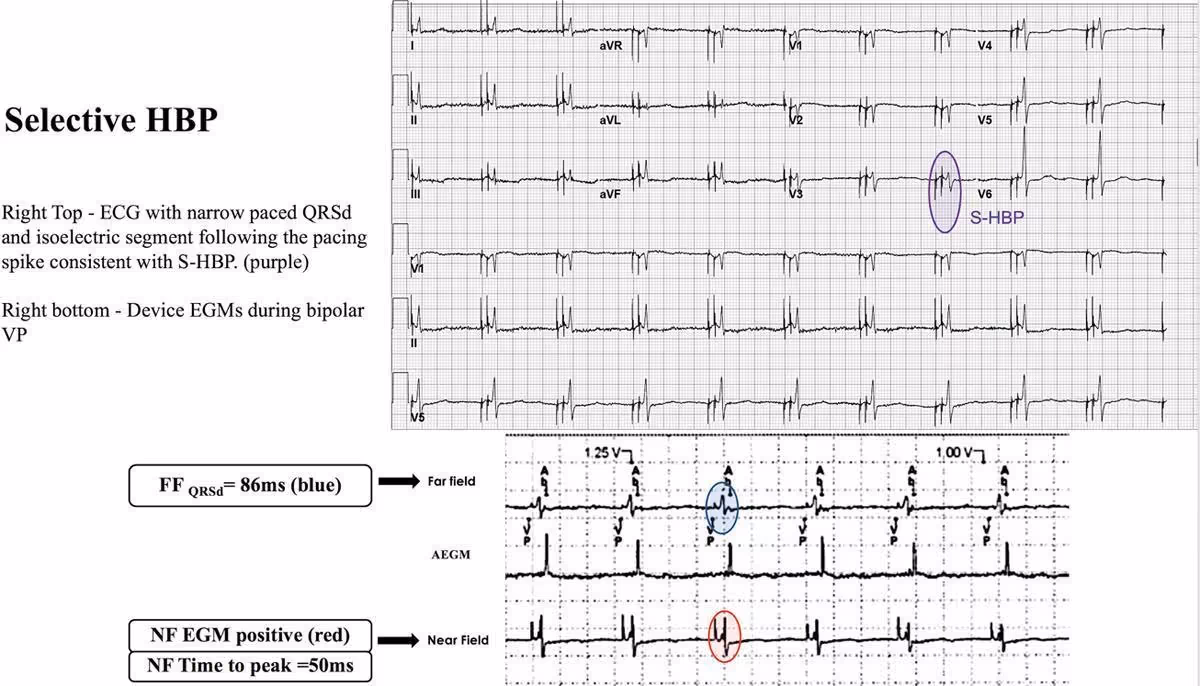

Obr. 3: Příklad selektivní Hisovské stimulace (S-HBP) a nález na EGM ze zařízení

úzký QRS komplex s izoelektrickou linií za spikem

na elektrogramu zařízení je vidět krátký izoelektrický segment, za kterým následuje no-flow elektrogram (červená oblast) s NFTime to peak 50ms od spiku

FFQRSd byla 86ms (modrá oblast)